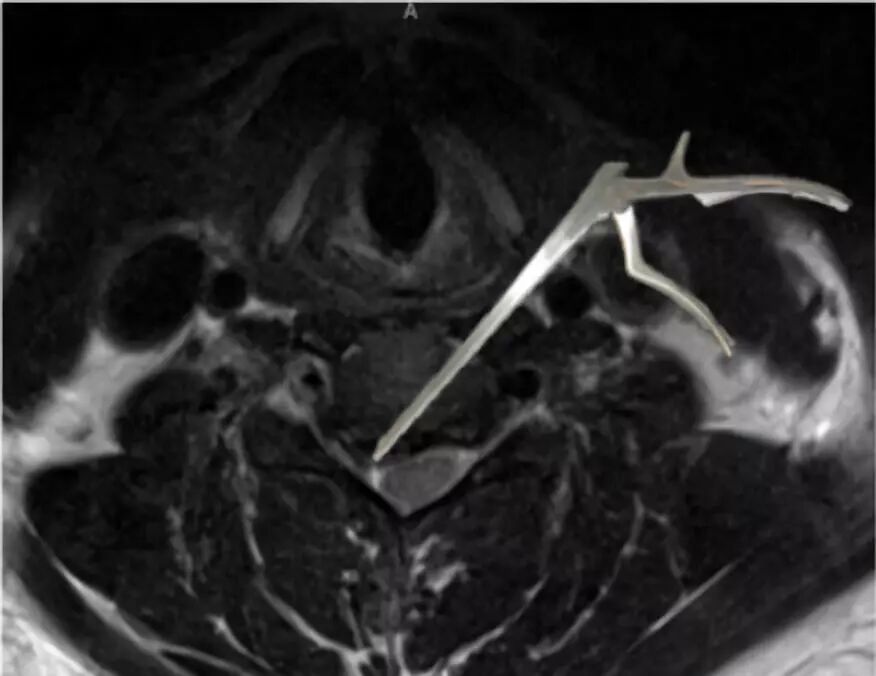

患者在4年半后再次出现急性颈痛发作。

但进行MRI复查证实在C5-6融合处减压稳定。